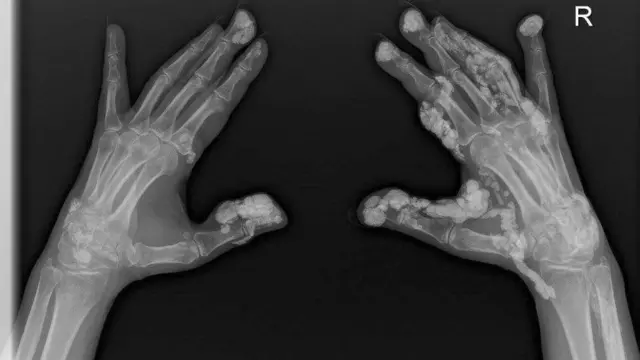

اس بیماری کا نام سکلیروڈرما ہے اور اس کی وجہ سے جے وردی کی جلد اور جوڑ سخت ہو چکے ہیں۔ یہ ان کے پھیپھڑوں پر بھی اثر انداز ہو رہی ہے جو کہ سخت سے سخت تر ہوئے جا رہے ہیں اور ڈاکٹروں کا کہنا ہے کہ اب ان کی حالت بد سے بدتر ہو گی۔

،تصویر کا ذریعہScleroderma & Raynauds UK